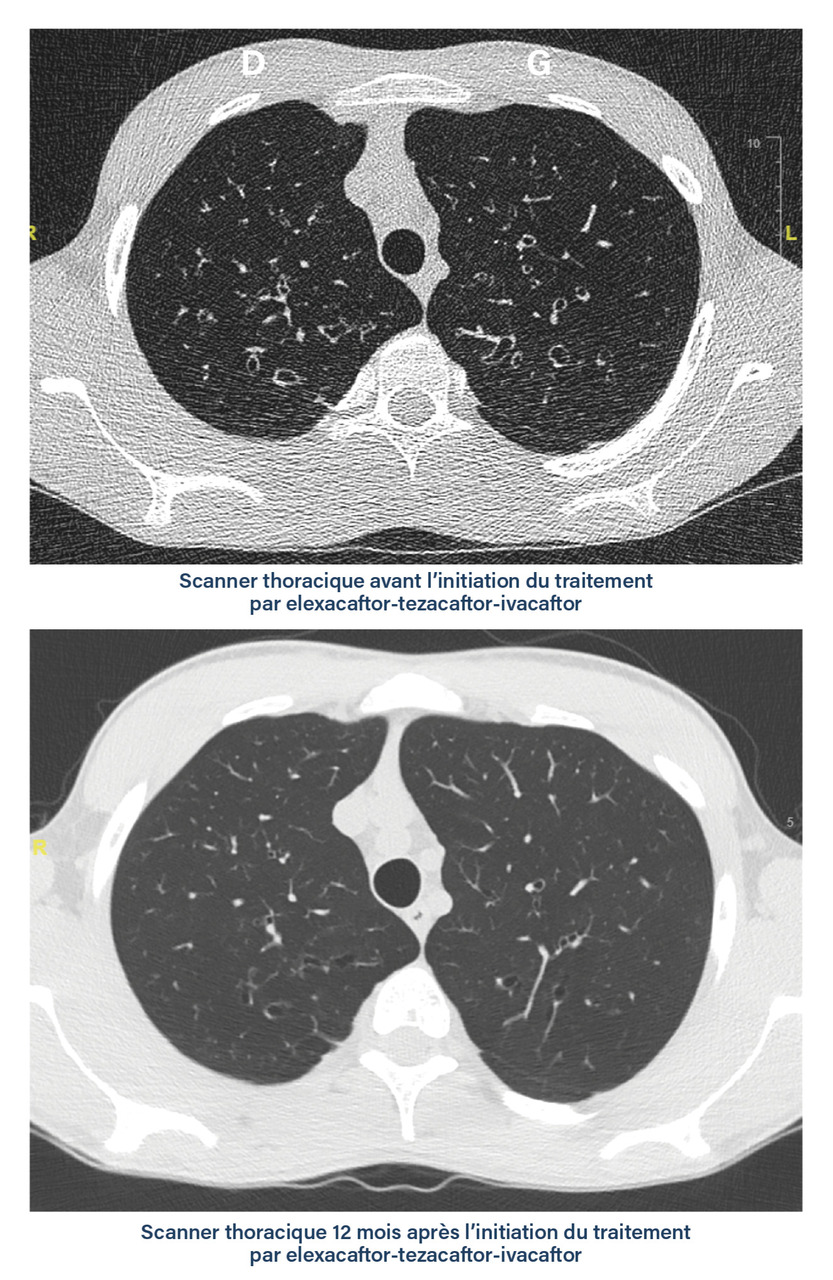

La plus grande sensibilité du scanner thoracique (le plus souvent non injecté) pour détecter des anomalies précoces à des doses de radiations ionisantes réduites (scanner low dose ou ultra low dose) a relégué au second plan la radiographie thoracique.4 Plusieurs types d’anomalie sont visibles sur les scanners thoraciques des patients, et ce dès le plus jeune âge  : DDB et épaississement des parois bronchiques, impactions mucoïdes, zones de trappage aérique, atélectasies. Certaines de ces anomalies sont réversibles sous traitement par modulateur de CFTR tel que la triple combinaison par elexacaftor-tezacaftor-ivacaftor (fig. 1).